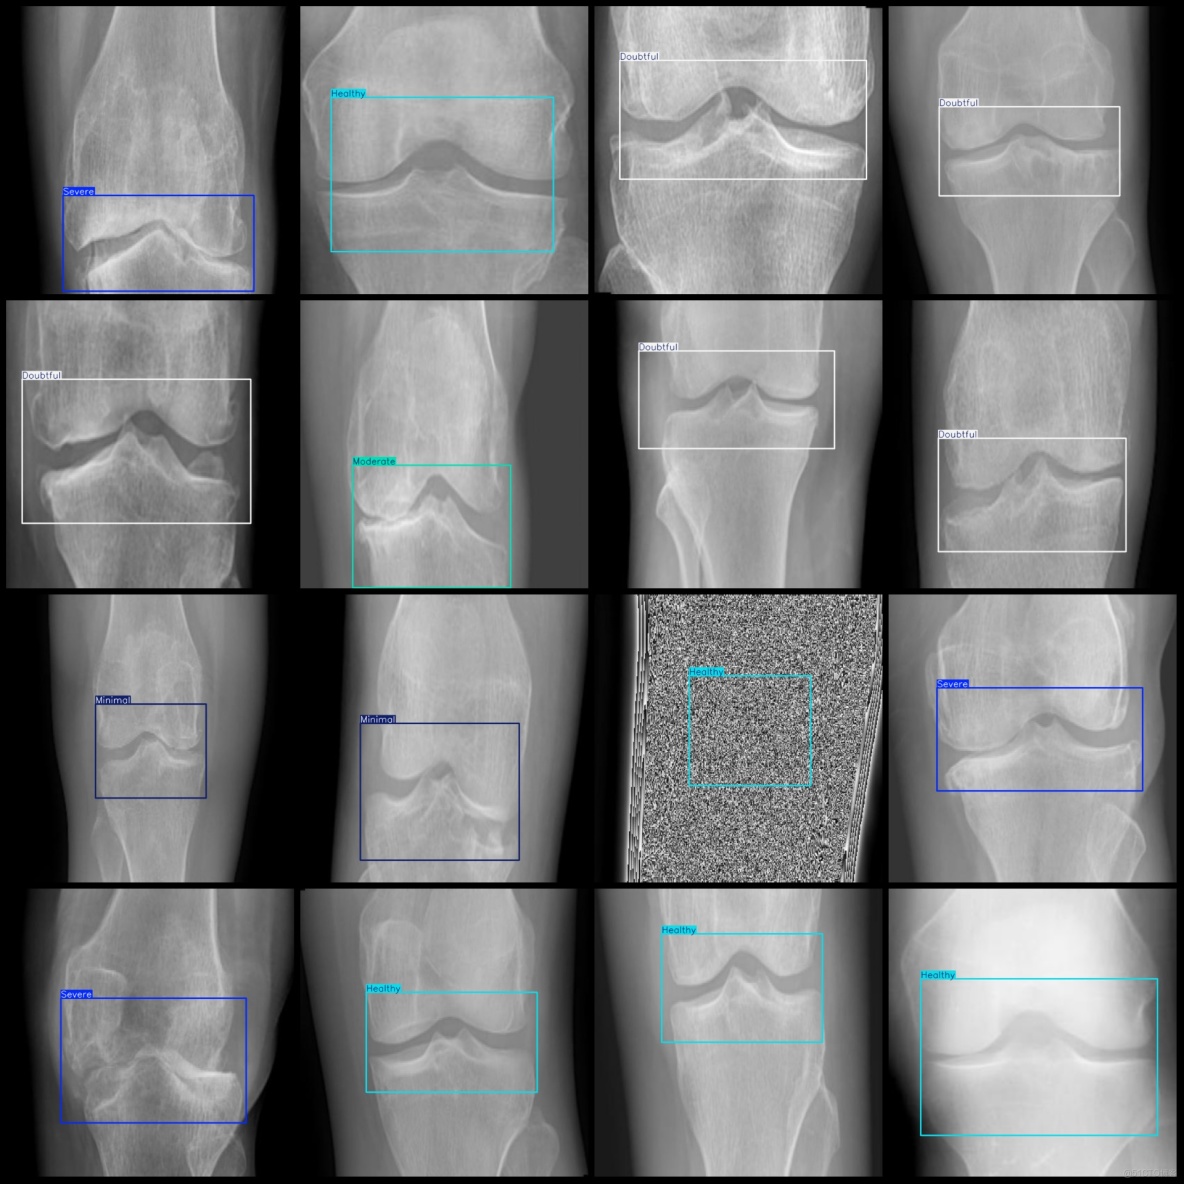

標註例子:

智慧醫療膝蓋骨關節炎嚴重程度檢測數據集VOC+YOLO格式8000張5類別_txt文件_03

智慧醫療膝蓋骨關節炎嚴重程度檢測數據集VOC+YOLO格式8000張5類別_xml文件_04

標註類別名稱(注意yolo格式類別順序不和這個對應,而以labels文件夾classes.txt為準):["Doubtful","Healthy","Minimal","Moderate","Severe"]

每個類別標註的框數:

Doubtful (待定) 框數 = 1414

Healthy (健康) 框數 = 3700

Minimal (極輕度) 框數 = 819

Moderate (中度) 框數 = 730

Severe (重度) 框數 = 1337